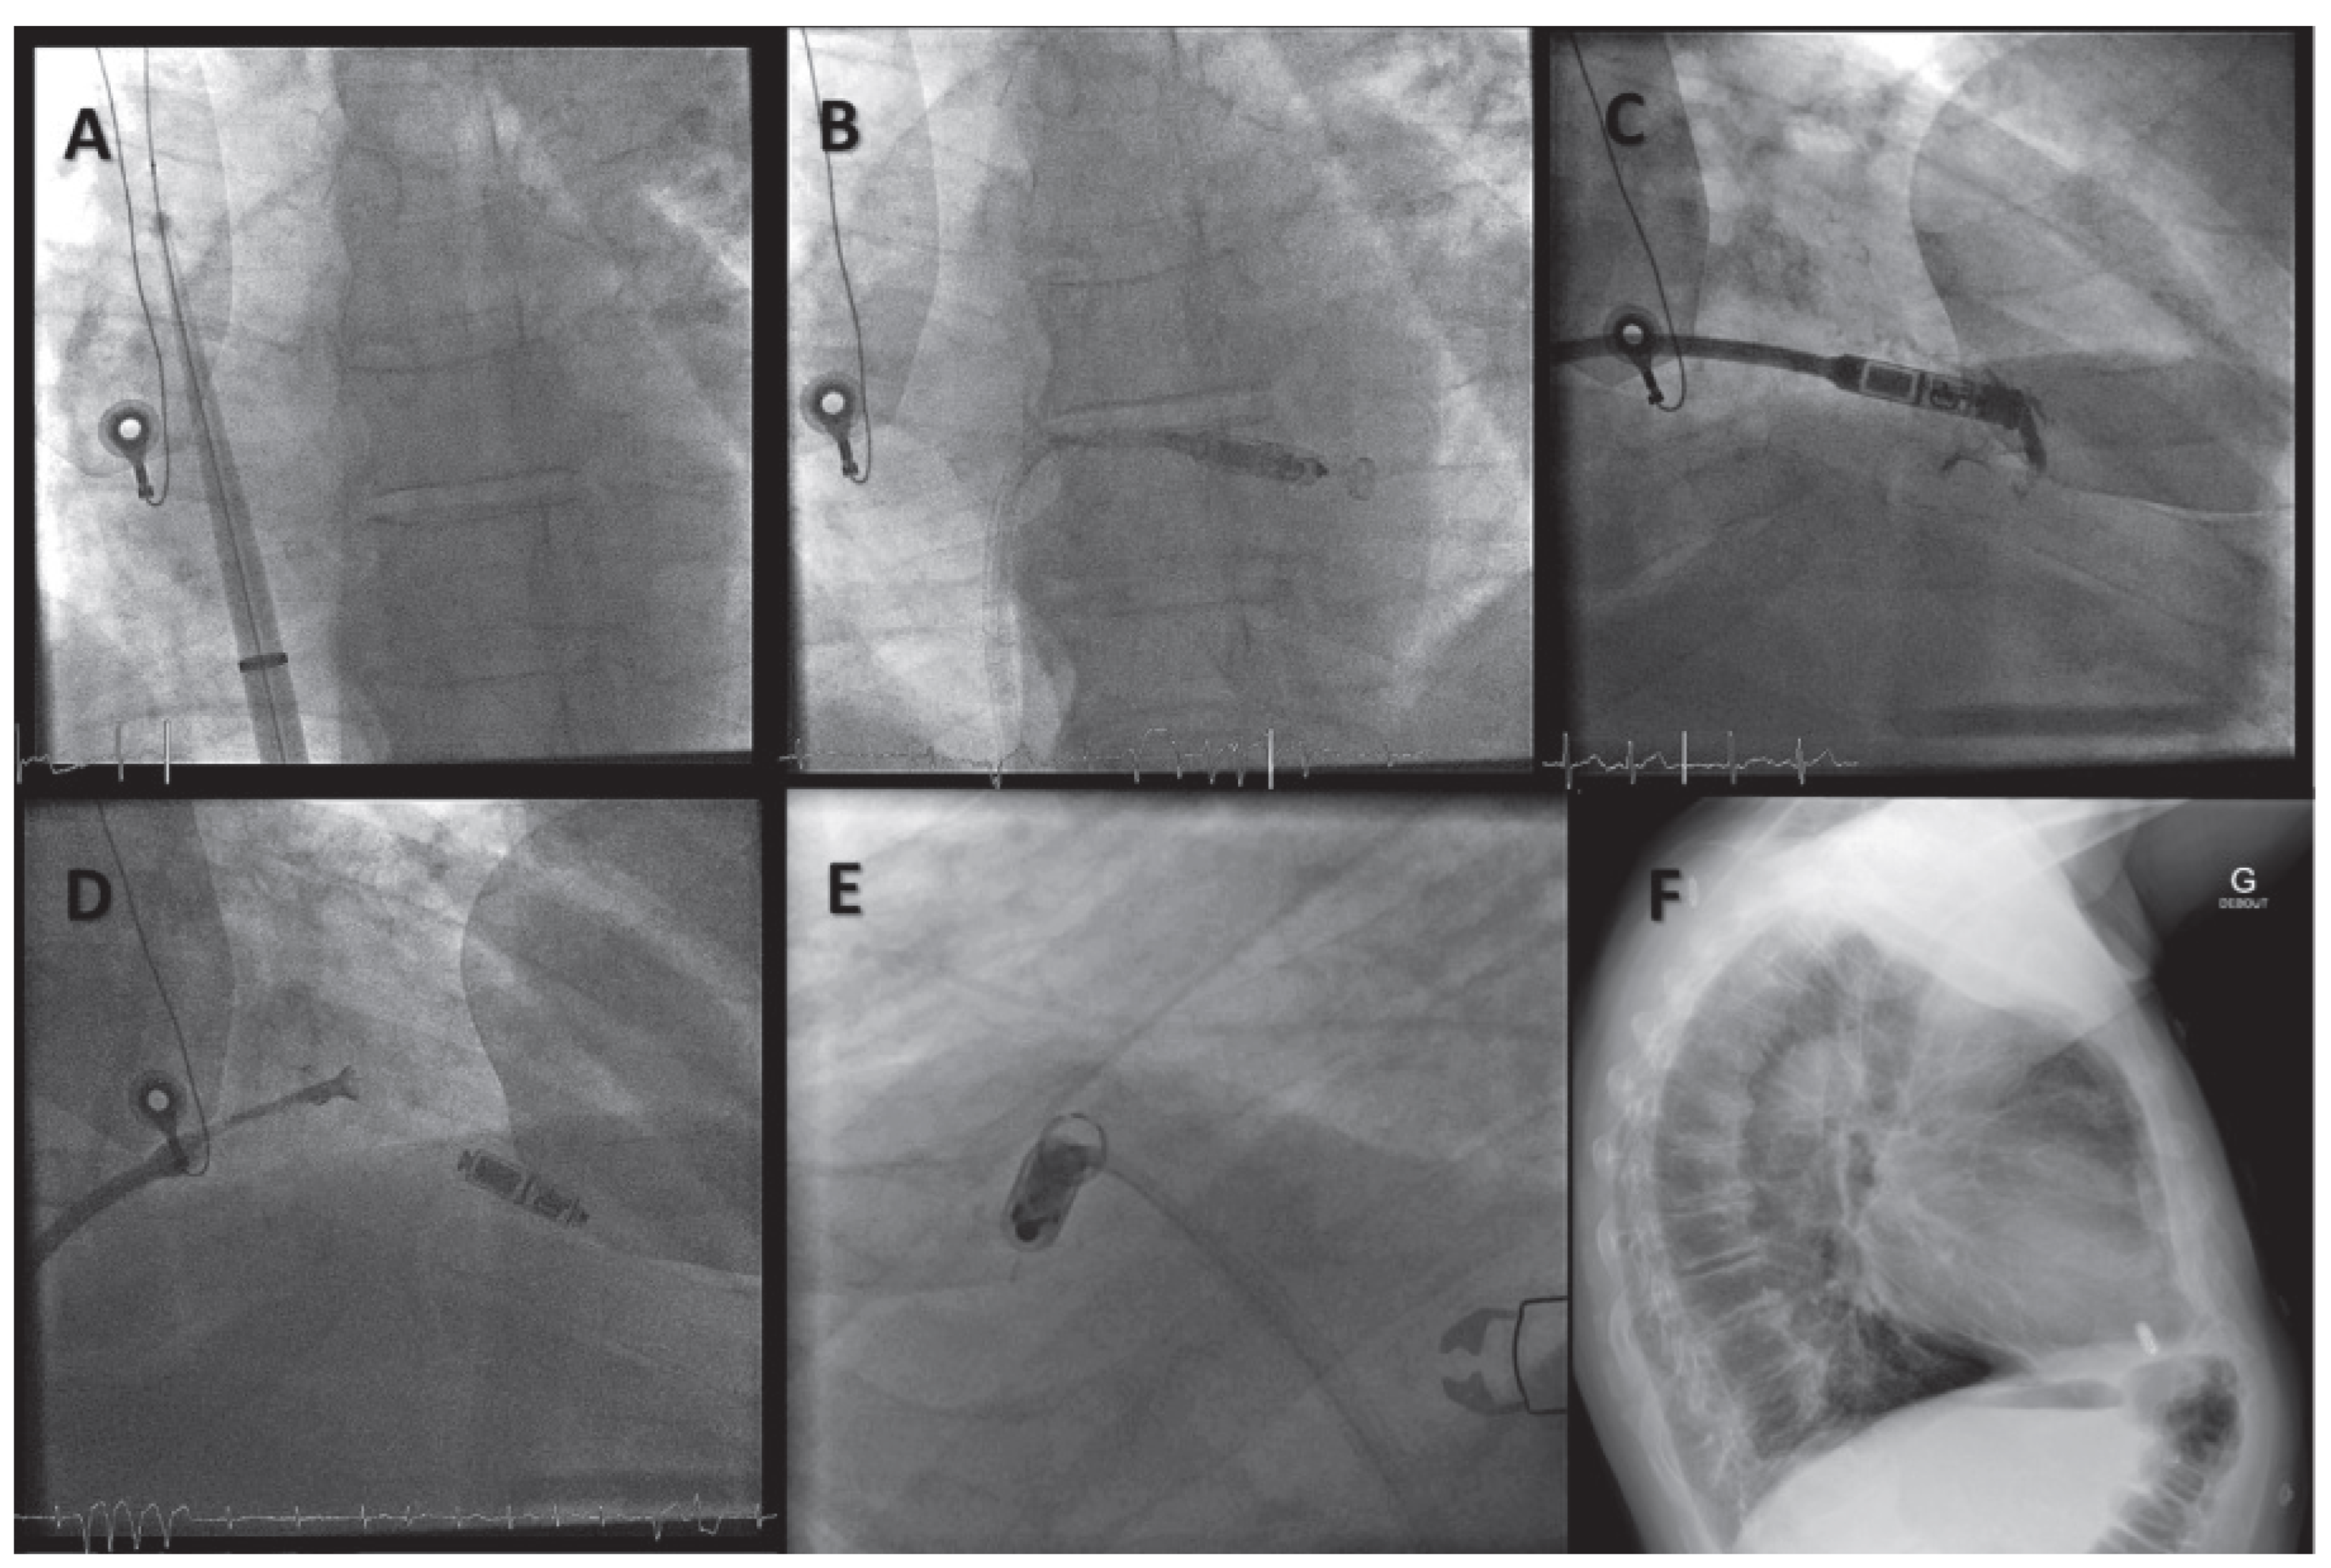

Implantation Procedures of Leadless Devices

Right Ventricular Pacing Systems

Wireless Cardiac Resynchronisation Therapy System